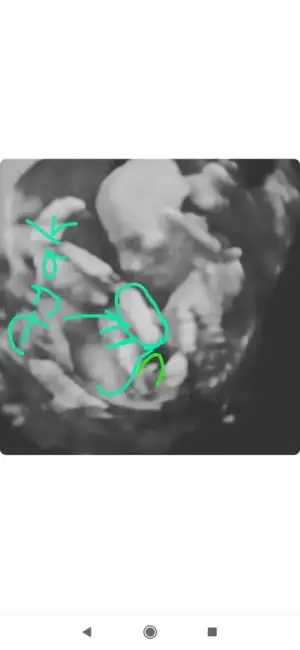

Ben cizmedim isegramdan bu sayfa çizdi cinsiyetini öğren diye bi sayfaSen ustunu cizmissin bilemedim simdi.baska bir dr a da gitsen imkanın vaktin varsa için rahat olur .

Evet o sayfa bana erkek dedi bugün öğrenmeye gideceğim bende hayırlısı olsunBen cizmedim isegramdan bu sayfa çizdi cinsiyetini öğren diye bi sayfa

Canım hayırlı haberle gel inşallahEvet o sayfa bana erkek dedi bugün öğrenmeye gideceğim bende hayırlısı olsun